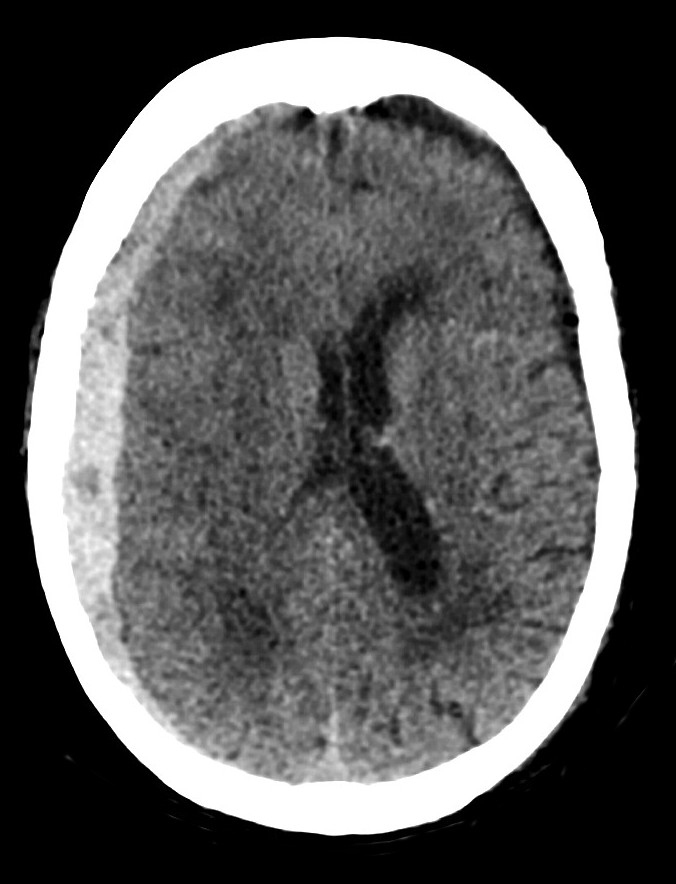

Question 12: Vous obtenez rapidement la coupe suivante

Il s’agit d’un hématome sous-dural aigu droit avec effet de masse sur la ligne médiane.

Après résolution de l’épisode convulsif et prise en charge chirurgicale de l’hématome sous-dural aigu, Jérôme est hospitalisé en réanimation où des mesures de neuroprotection sont mises en place.